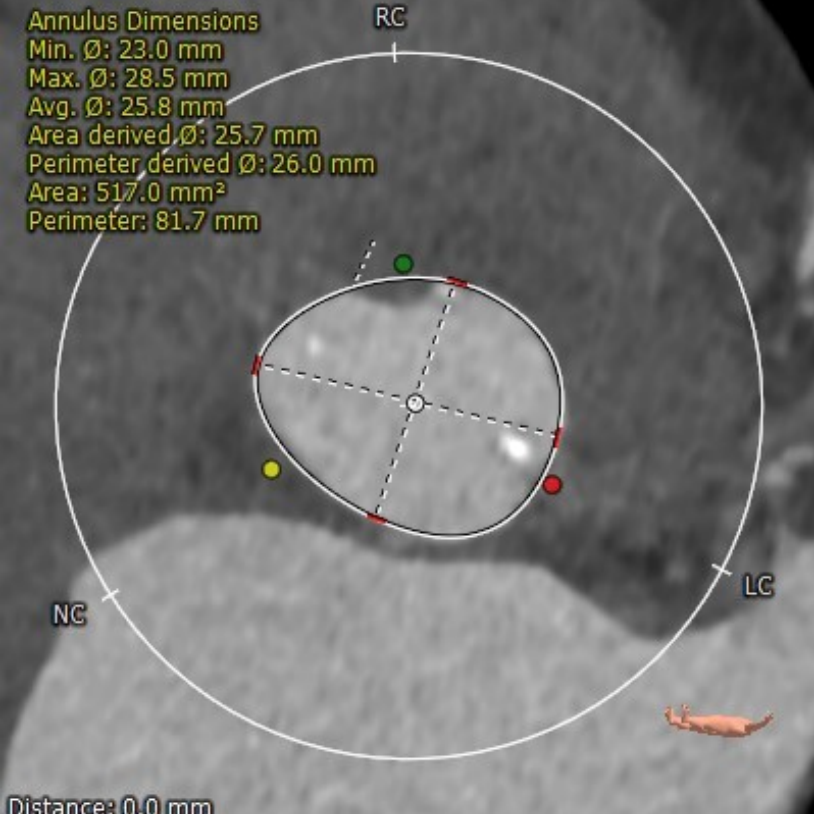

CT评估报告

瓣环平均直径:26.0 mm,左室流出道平均直径:28.1 mm

升主动脉未见明显扩张,心脏角度:34°

左冠开口高度:16.4 mm;右冠开口高度:15.6 mm

钙化积分:606 mm³,重度钙化

左冠瓣叶长度:19.2 mm,右冠瓣叶长度:17.4 mm